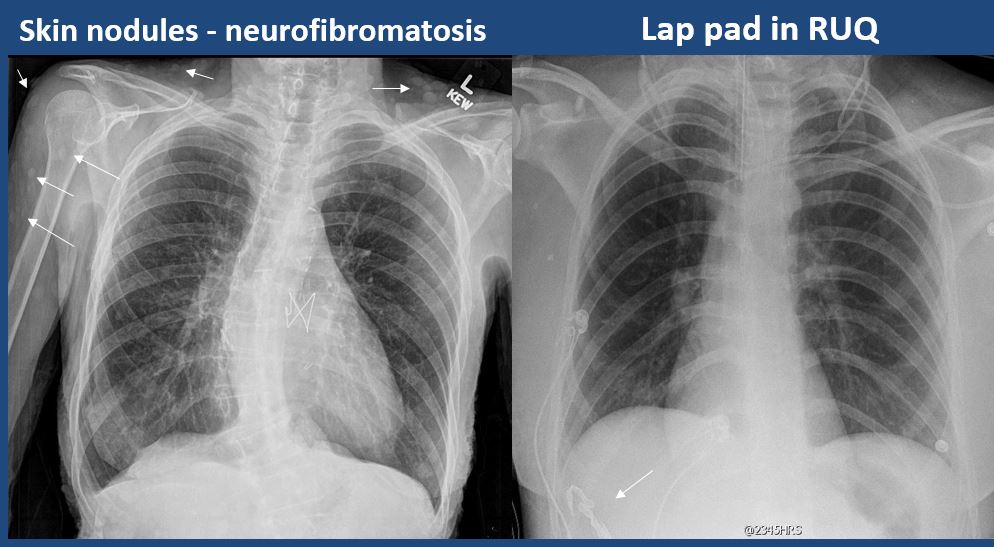

There is subcutaneous emphysema, focal or diffuse soft tissue abnormality, radiopaque foreign body, or post-surgical change or hardware. |

yes | NA |